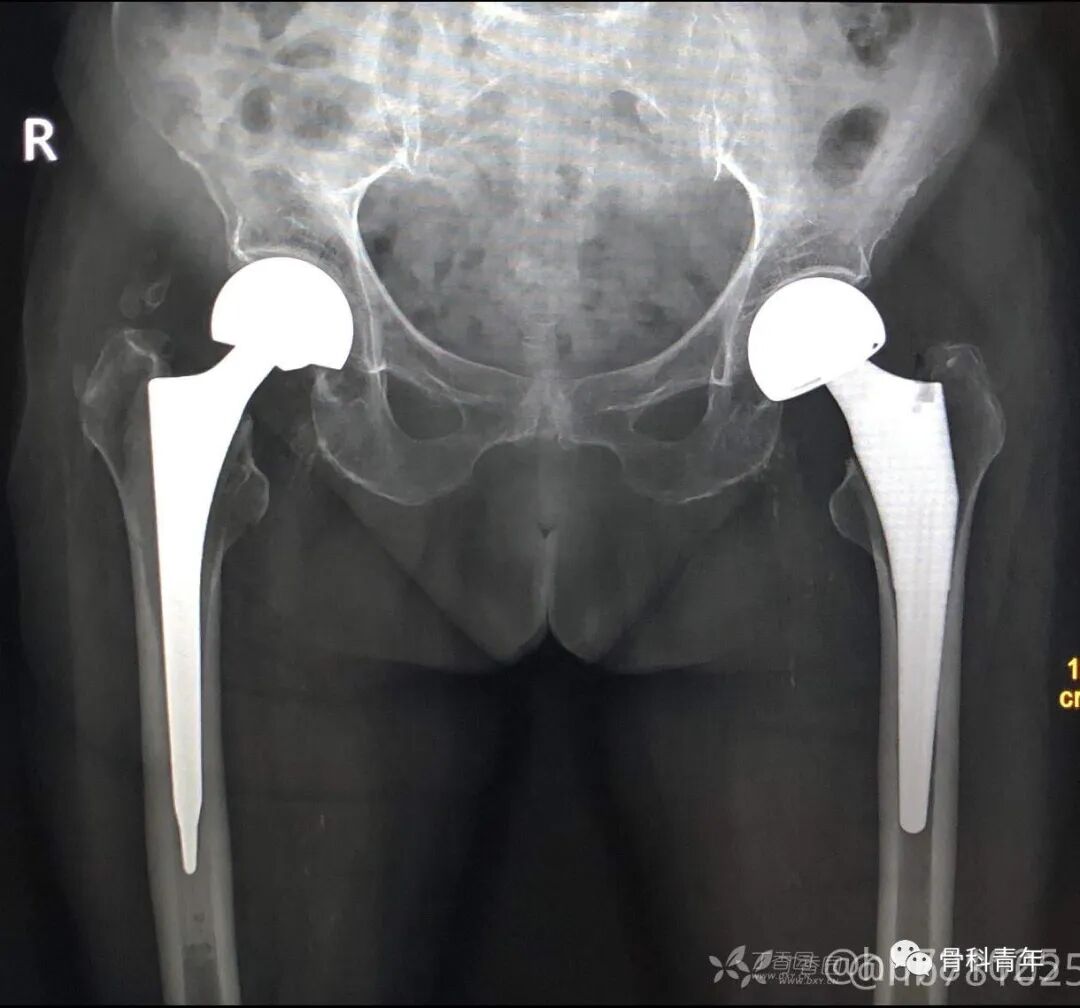

2.全髋关节置换